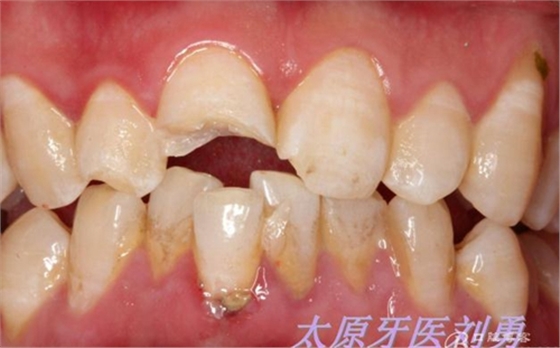

患兒8歲,不慎摔倒導(dǎo)致上前牙折斷,來(lái)院就診,行根尖片檢查,根尖孔尚未閉合,且呈喇叭口狀,就診時(shí)患兒自己帶來(lái)了折裂的牙齒碎片,口內(nèi)檢查,A1折斷1/2,斷端可見(jiàn)兩處 露髓點(diǎn),一處直徑約為1.5mm,一處約為1mm,未見(jiàn)明顯出血,B1近中切角缺損,考慮到患兒根尖孔尚未閉合,于是決定保留牙髓(若根尖孔已經(jīng)閉合,則摘除牙髓,纖維樁加強(qiáng)粘結(jié)固定折裂碎片。不多說(shuō)了,還是看術(shù)前照片:

另外一例為本人高中同學(xué),同樣不慎摔倒,導(dǎo)致A1折裂,露髓,且舌側(cè)有一碎片折裂至齦下3mm左右,先看術(shù)前圖片:

術(shù)前如下: